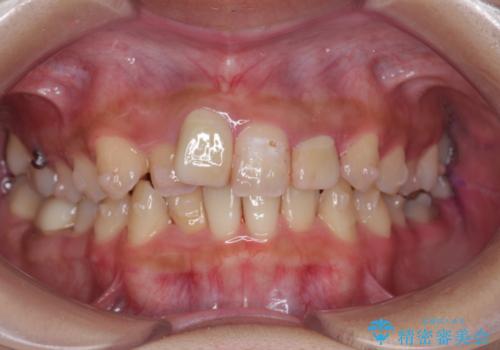

前歯のがたつき 保険治療の前歯の被せ物もやりかえたい

- 前歯のがたつきを主訴に来院。

保険治療の被せ物が前歯に2本あり、矯正治療で移動後にセラミックでやり替えを行っています。

右上のかみ合わせがずれていたため、インプラント矯正を行い、奥歯を後ろに下げて治療しています。